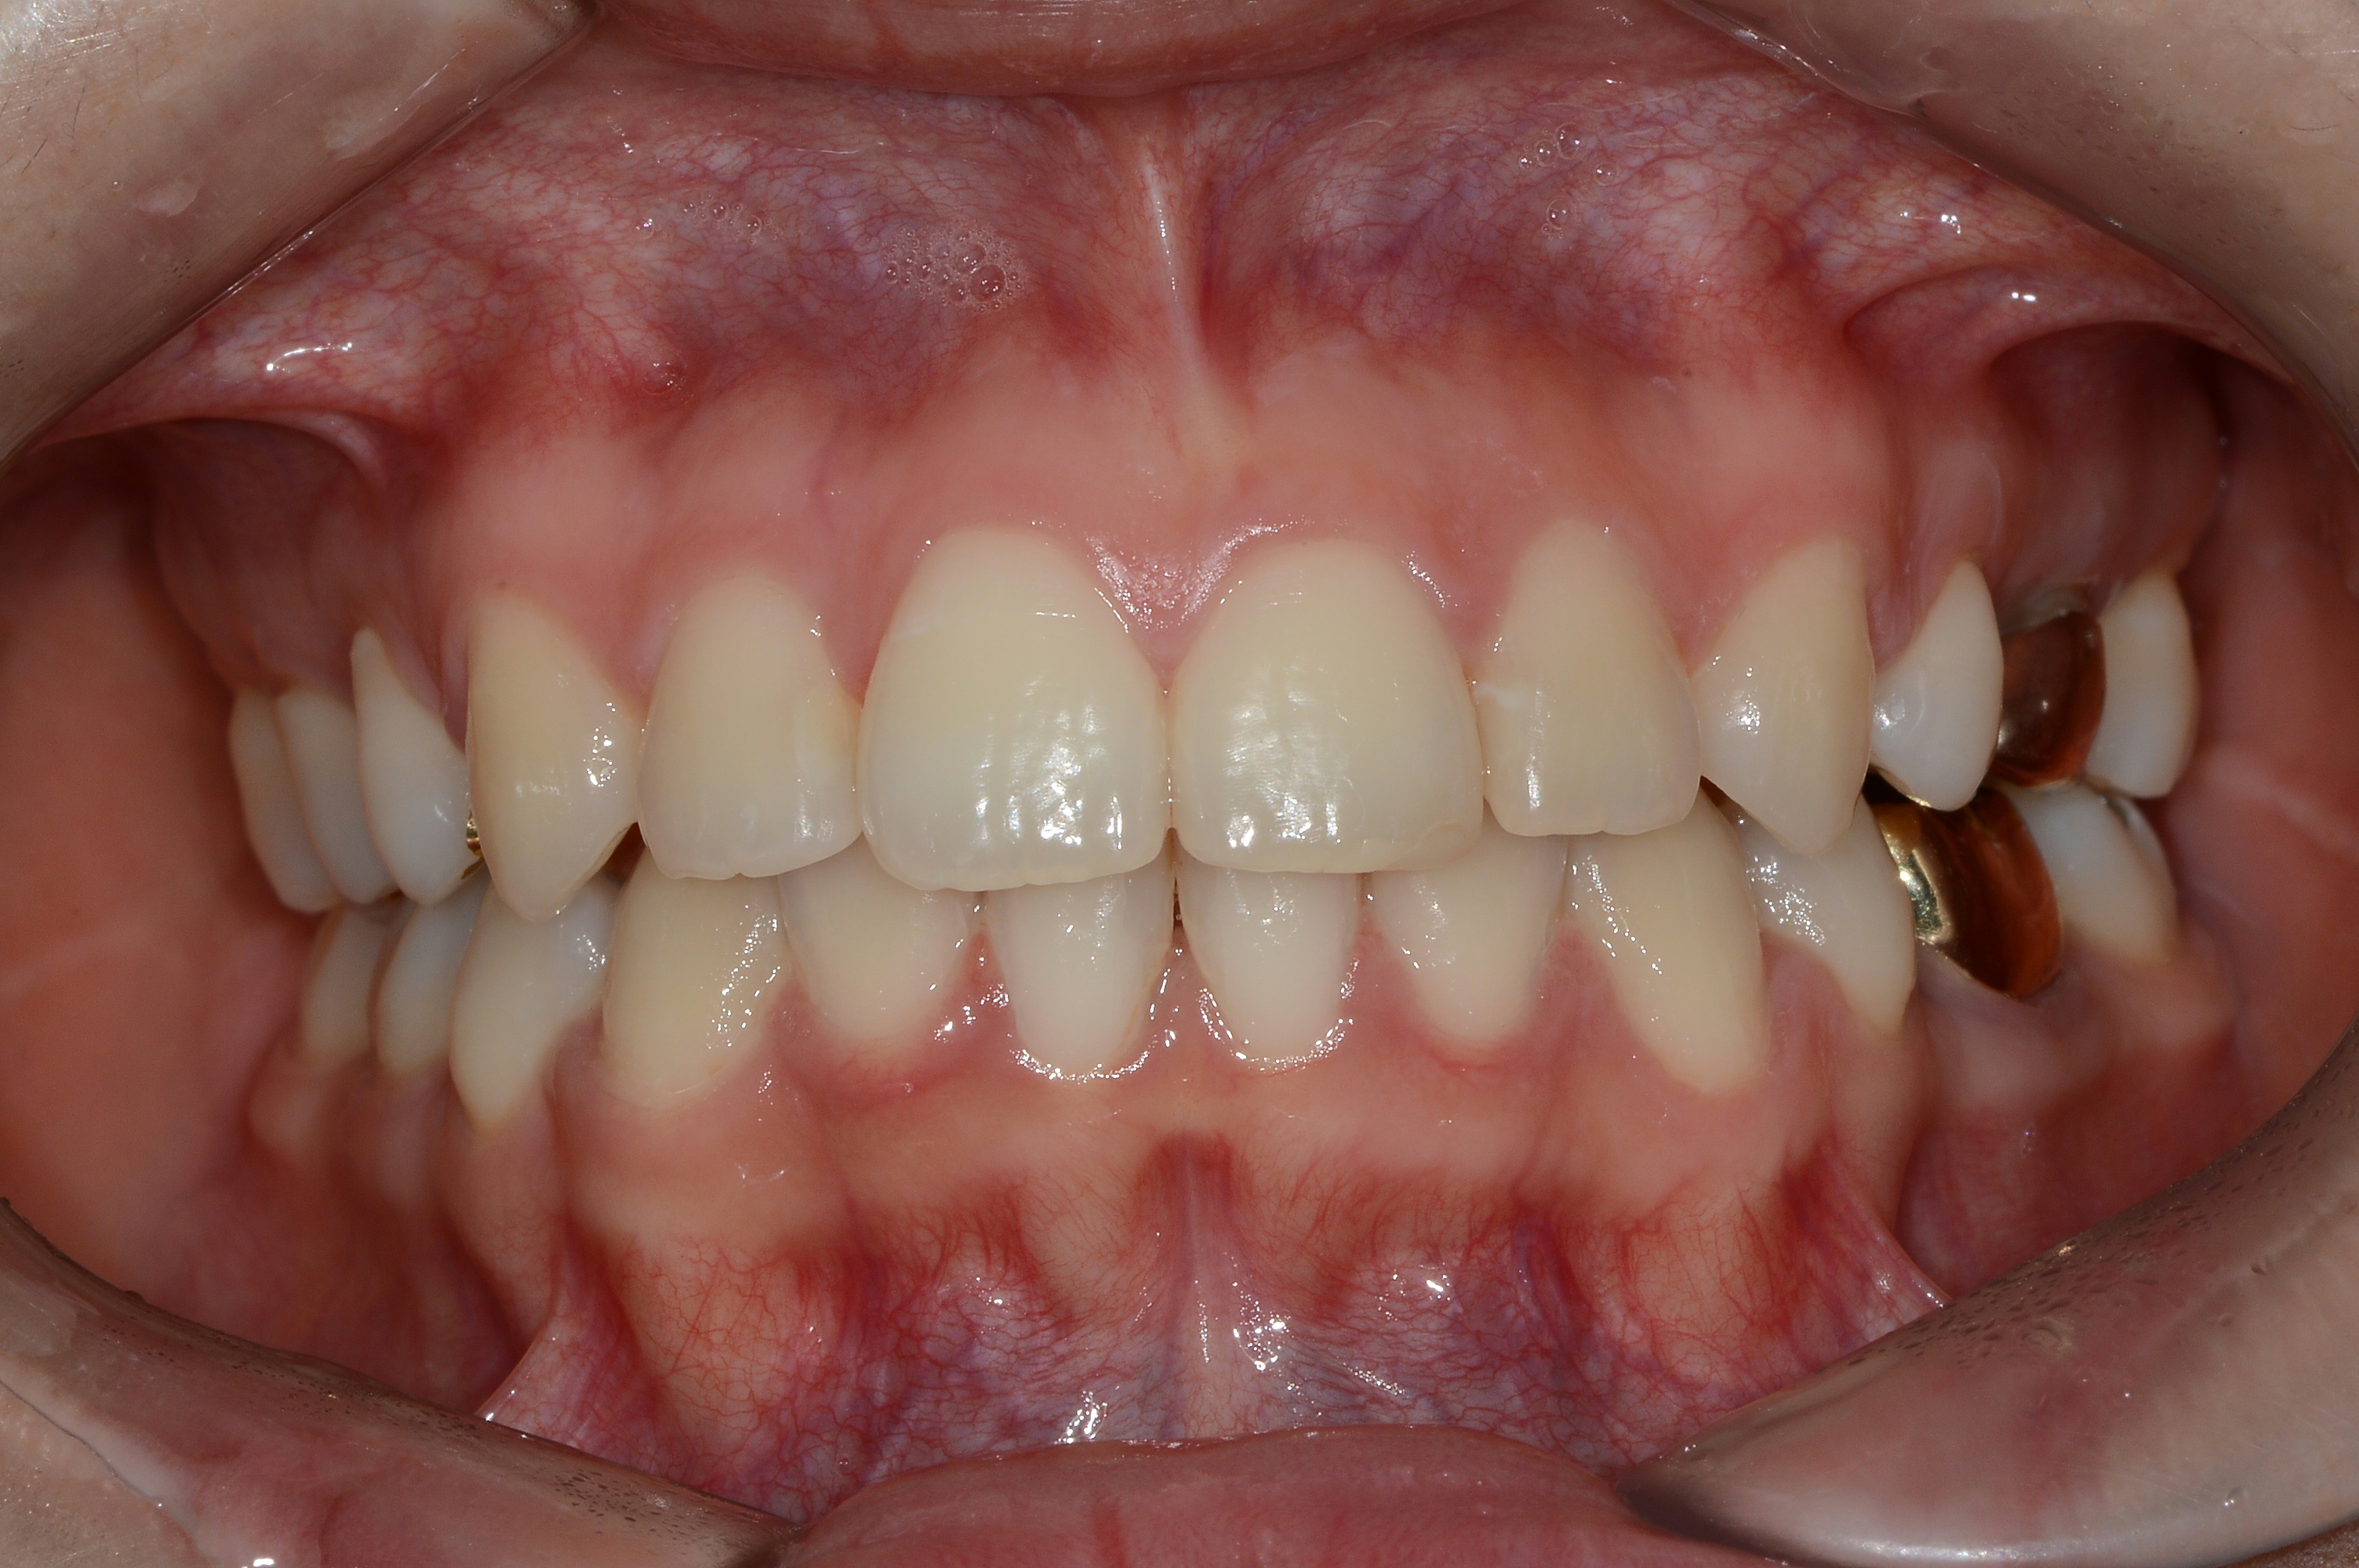

치료 후 사진입니다.